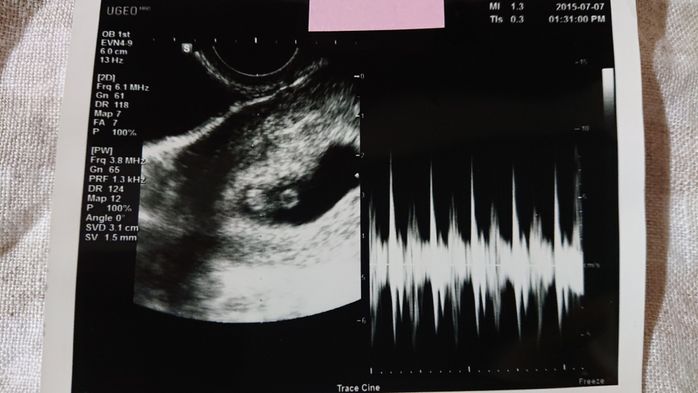

《妊娠5週目のエコー写真》

初めてのエコー検査からちょうど1週間後、赤ちゃんがおなかにやってきてくれたか、再度、確認する日がやってきました。まだ、赤ちゃんの姿は見えないけれど、胎嚢という赤ちゃんが育つためのお部屋が出来ているのを確認できました。胎嚢はエコー写真の黒丸部分です。私自身、「自分の体は妊娠できるのか」と長年不安だったので、前回は何も写っていなかったエコー写真を見たときは不安でしたが、今回は、くっきりと赤ちゃんのお部屋である胎嚢を見つけることができ、感動しました。